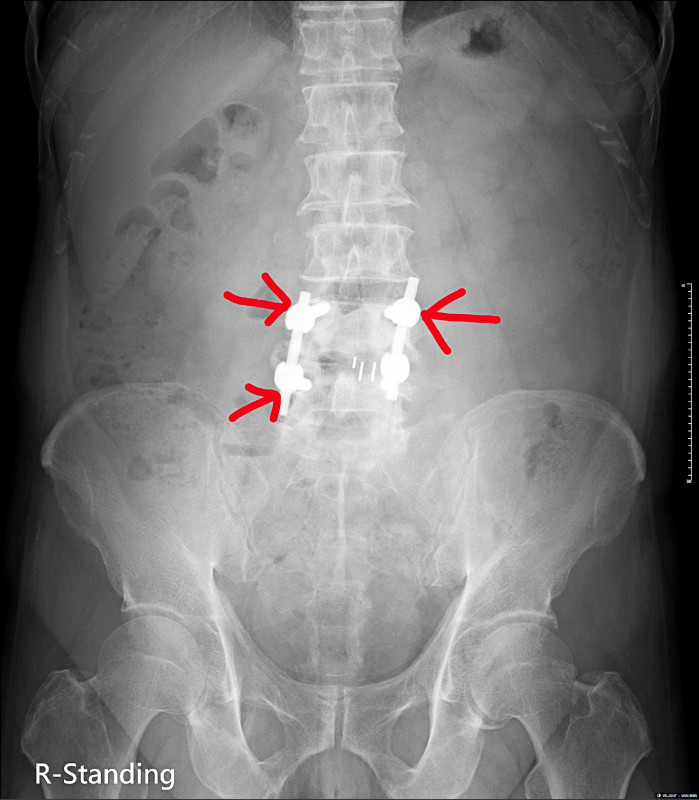

因為前述症狀,前來林口長庚醫院脊椎科門診。先幫他安排脊椎X光檢查,可以看到之前手術的釘子有鬆脫的情形(圖1),同時人工椎間盤墊片有向後外側滑脫的情形(圖2)。後續幫吳先生安排腰椎核磁共振(圖3),發現人工椎間盤墊片有向後壓到神經。吳先生的症狀和影像上的發現是相符的,因此向他解釋後續治療的方向。